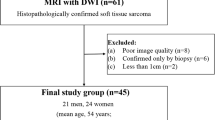

From June 2016 to January 2022, we retrospectively evaluated 64 consecutive patients with extremity STS who underwent post-surgical MRI for scheduled follow-up (n = 52) or because of Whoops surgery or with positive margins after planned excision (n = 12).

All examinations were performed with a 1.5 Tesla MR Scanner (GE Signa HDXT TwinSpeed—software v. 15.0) using the proper coil according to the anatomic region and clinical setting. The MR protocol included conventional imaging (T1 and T2 weighted, STIR, GRE) and DWI using b = 0, 1000, a relatively high b to minimize perfusion effect and mitigate the effects of “T2-shine through.”

Single-shot echo planar DWI was performed choosing the most appropriate plane and a field of view large enough to include the edges of the scar adjacent post-therapeutic alterations (15-42 cm) with the following parameters:

TR = 2800–7000 ms, TE = the lowest possible value (53-75 ms), matrix phase value = 256, matrix frequency value = 86–128, slice thickness = 3–5 mm, number of averages = 5–7 (for both b values: 0 and 1000), receiver bandwidth = 250 kHz, parallel imaging (ASSET; acceleration factor 2).

Study population included 64 patients, 35 males and 29 females, with age range 10–94 and mean age 52.36 years. Pre-operative histological diagnoses and anatomic sites of tumors are reported in Table 2.